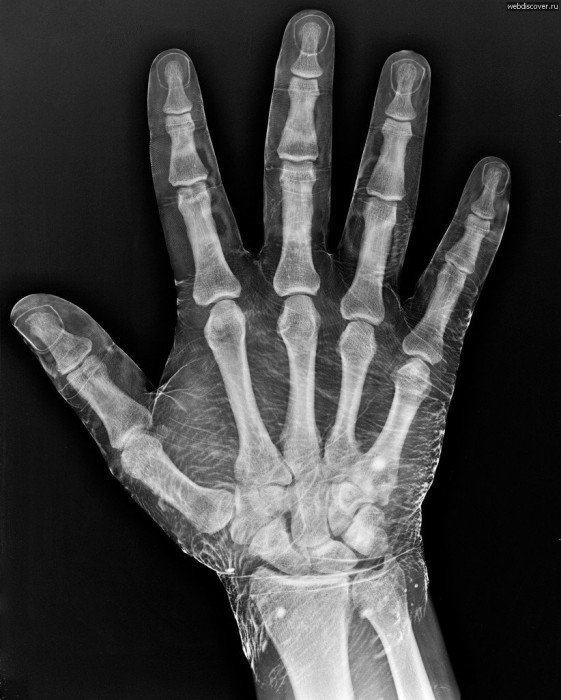

Вопросом, почему человек на ногах и руках имеет именно пять пальцев, учёные интересуются уже давно. Совсем недавно в ходе экспериментов было доказано, что ранее озвученная теория о том, что пальцы людей произошли из плавников рыб, является верной.

Последняя гипотеза говорит, что руки человека или других животных с пятью пальцами произошли из плавников рыб. Как известно, плавники рыб состоят из тонких лучей с перепонками. В ходе эволюции именно плавники и стали прообразами пальцев, а также ног и лап. Так как рыбы перемещаются в воде именно при помощи плавников, в процессе эволюции плавники и дальше стали играть роль движущей силы, трансформировавшись в ноги, лапы, руки и пальцы. Такой переход заметен у ископаемых тетраподов (первые четвероногообразные, жившие около 380 млн. лет назад). Как известно, тетраподы произошли от кистепёрых рыб. Изучая последовательную цепочку превращения рыб в тетраподов, было обнаружено, что четыре ноги были образованы именно из плавников, однако у ископаемых животных число пальцев было больше.

Канадские биологи из Монреальского университета и Института клинических исследований пошли ещё дальше и, чтобы доказать верность данной теории, провели детальные исследования с применением генных технологий. В ходе исследований было выяснено, что за формирование лучей плавников рыб и пальцев человека отвечают одни и те же гены — hoxa11 (рыб) и hoxa13. Однако, всё же, гены различаются по своей работе: у рыб они функционируют в клетках, образующих перекрывающиеся друг с другом области, а у человека они работают в отдельных участках зачатка конечности. Пересадив рыбий ген hoxa11 в зародыш мыши, у которого ещё не начали формироваться пальцы, учёные получили животное с семью пальцами. Таким образом исследователи пришли к выводу, что пять пальцев — это мутация последовательностей ДНК, которая была связана с изменением образа функционирования древних животных, переменивших свой образ жизни.